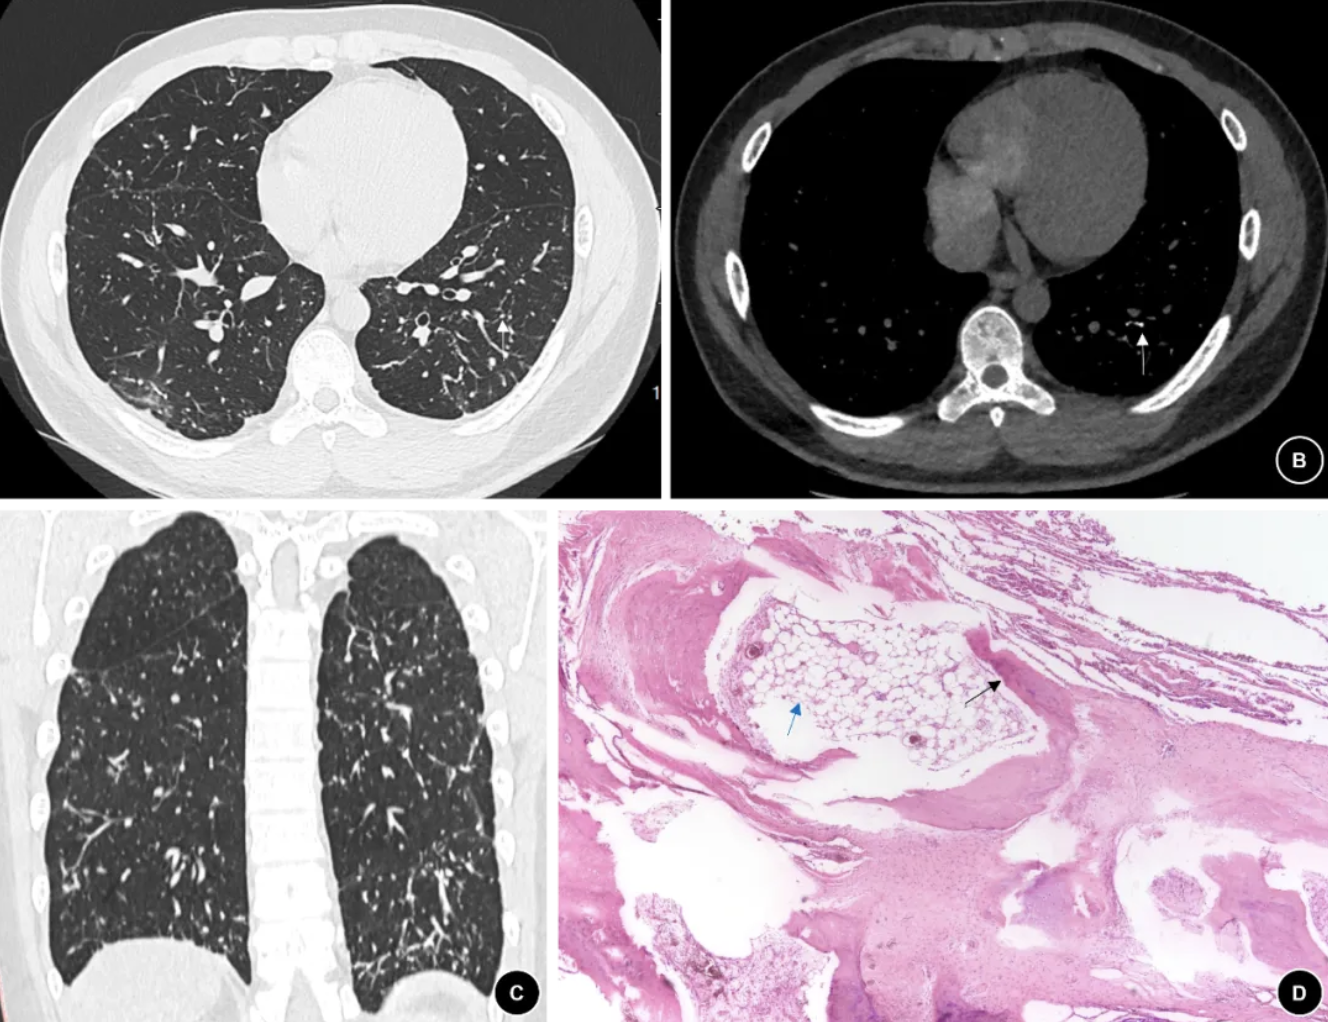

图 1. (例1患者)2022年9月胸部CT,肺窗(A)、纵隔窗(B)、冠状面(C)显示双肺多发性高密度小结节伴钙化及分支良好的细线状影,纵隔窗可见结节钙化影,分布较稀疏(白色箭头);(D)SLB病理组织学显示肺内成熟骨组织(黑色箭头),其中可见脂肪组织(蓝色箭头),部分肺实质受压、塌陷(HE染色 ×100)。

4. 胸部影像学及肺功能表现:4例的胸部CT(图1-4 A-C)主要表现为双肺弥漫性高密度小结节伴钙化、散在分支样细线状影、胸膜轻度增厚。其中2例患者完善99mTc-亚甲基二膦酸盐(Methylene diphosphonate, MDP )全身骨显像(ECT)发现双肺放射性摄取弥漫增高,考虑骨外摄取(图2-3 D-E)。肺功能测试显示3例轻度阻塞性通气功能障碍, 1例限制性通气功能障碍,3例伴弥散功能轻度下降(表2)。

5. 病理学表现:4例诊断均经肺活检病理结果证实。1例在胸腔镜下行外科肺活检(Surgical lung biopsy, SLB),术中发现胸膜表面弥漫性分布粟粒样质硬结节,行楔形切口留取样本;2例行经支气管冷冻肺活检(transbronchial cryobiopsy, TBCB),获得3-4块直径约0.5 cm的肺组织标本;1例行经支气管肺活检(Transbronchial lung biopsy, TBLB)。病理主要表现为镜下观察到肺内成熟骨组织(黑色箭头),其中部分可见脂肪组织(蓝色箭头)(图1D、2F,、3F、4D)。